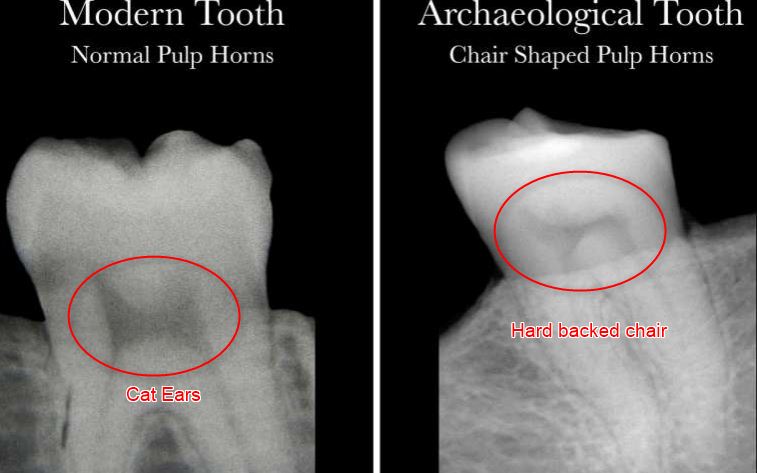

• “The pulp shape in a healthy person's tooth resembles an arch topped by two cat ears, while the pulp shape of a person who has had a severe deficiency of Vitamin D is asymmetrical and constricted, and typically looks like the profile of a hard-backed chair.”

This study investigates morphological changes in pulp chambers of living and archaeological individuals with past vitamin D deficiency. Living individuals (n = 29), four with detailed medical and dental records and three groups of archaeological individuals (n = 25) were radiographed; selected individuals were further evaluated histologically for the presence of incremental interglobular dentin (IIGD), indicative of deficiency (28 living; 17 archaeological). Measurements of pulp horns/chambers from radiographs were conducted to quantify morphological observations. One group had clear skeletal evidence of rickets from St. Matthew, Quebec (n = 1) and St. Jacques, France (n = 4); a second group had slight skeletal indicators from Bastion des Ursulines, Quebec (n = 6); and a third group lacked both skeletal and radiological evidence of deficiency from St. Antoine (n = 6) and Pointe-aux-Trembles (n = 4). Results showed archaeological individuals with clear and slight skeletal evidence of past deficiency displayed constricted or chair shaped pulp horns. Living individuals with deficiency exhibited similar pulp chamber morphology. Radiographic pulp horn/chamber measurements corroborated morphological findings and significant differences were found in pulp horn/chamber measurements between those with and without deficiency. Results suggest that radiograph assessment of teeth can be used as a screening technique to elucidate patterns of deficiency and select individuals for microCT or histological assessment.